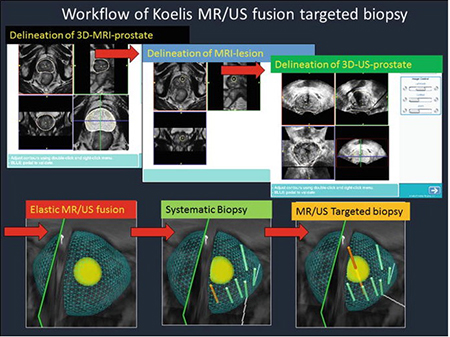

Για την διάγνωση του καρκίνου του προστάτη στον όμιλο ΙΑΤΡΟΠΟΛΙΣ πραγματοποιούνται βιοψίες, μέσω της νέας παγκοσμίου εμβέλειας μεθόδου: 3D MRI/TRUS SOFT ELASTIC FUSION.

Με την νέα μέθοδο επιτυγχάνεται με απόλυτη ακρίβεια η λήψη υλικού βιοψίας αποκλειστικά και μόνο, από τα προς διερεύνηση εντοπισμένα ύποπτα σημεία, που έχουν ήδη αναδειχθεί στην προηγηθείσα πολυπαραμετρική μαγνητική τομογραφία προστάτη.

- Την ελαστική συγχώνευση τρισδιάστατων εικόνων Υπερηχογραφήματος και Μαγνητικής Τομογραφίας σε πραγματικό χρόνο μέσω του λειτουργικού συστήματος εντοπισμού Organ-Based Tracking Fusion( OBT Fusion).

- Aπεικόνιση του προστάτη σε τρισδιάστατη μορφή.

- Λήψη βιοψίας σε εικονικό και πραγματικό χρόνο

Ακολουθούν Εικόνες

WORKFLOW OF ELASTIC FUSION BIOPSY